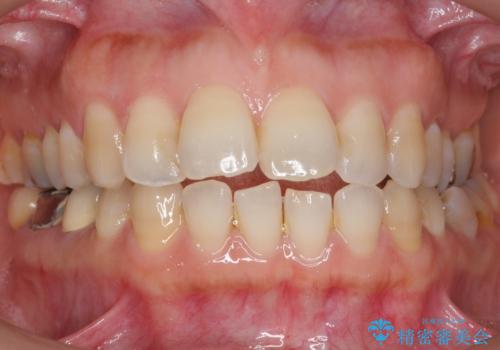

奥歯でしっかり噛むことができるようになり、喜んで頂けました。

セラミッククラウンの審美的な仕上がりにもご満足頂けました。

クラウンの種類:ベレッツァクラウン(右下76)、ジルコニアクラウン スタンダード(右下5)